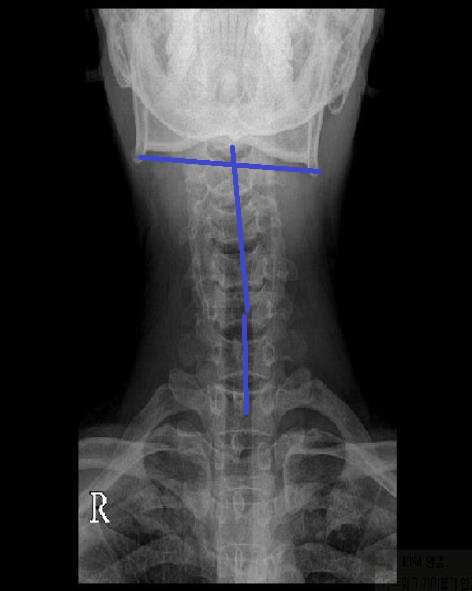

진단 : 상부 경추에 문제가 발견되었고 요추와 골반도 이상이 있었으나 요통 호소는 없었습니다.